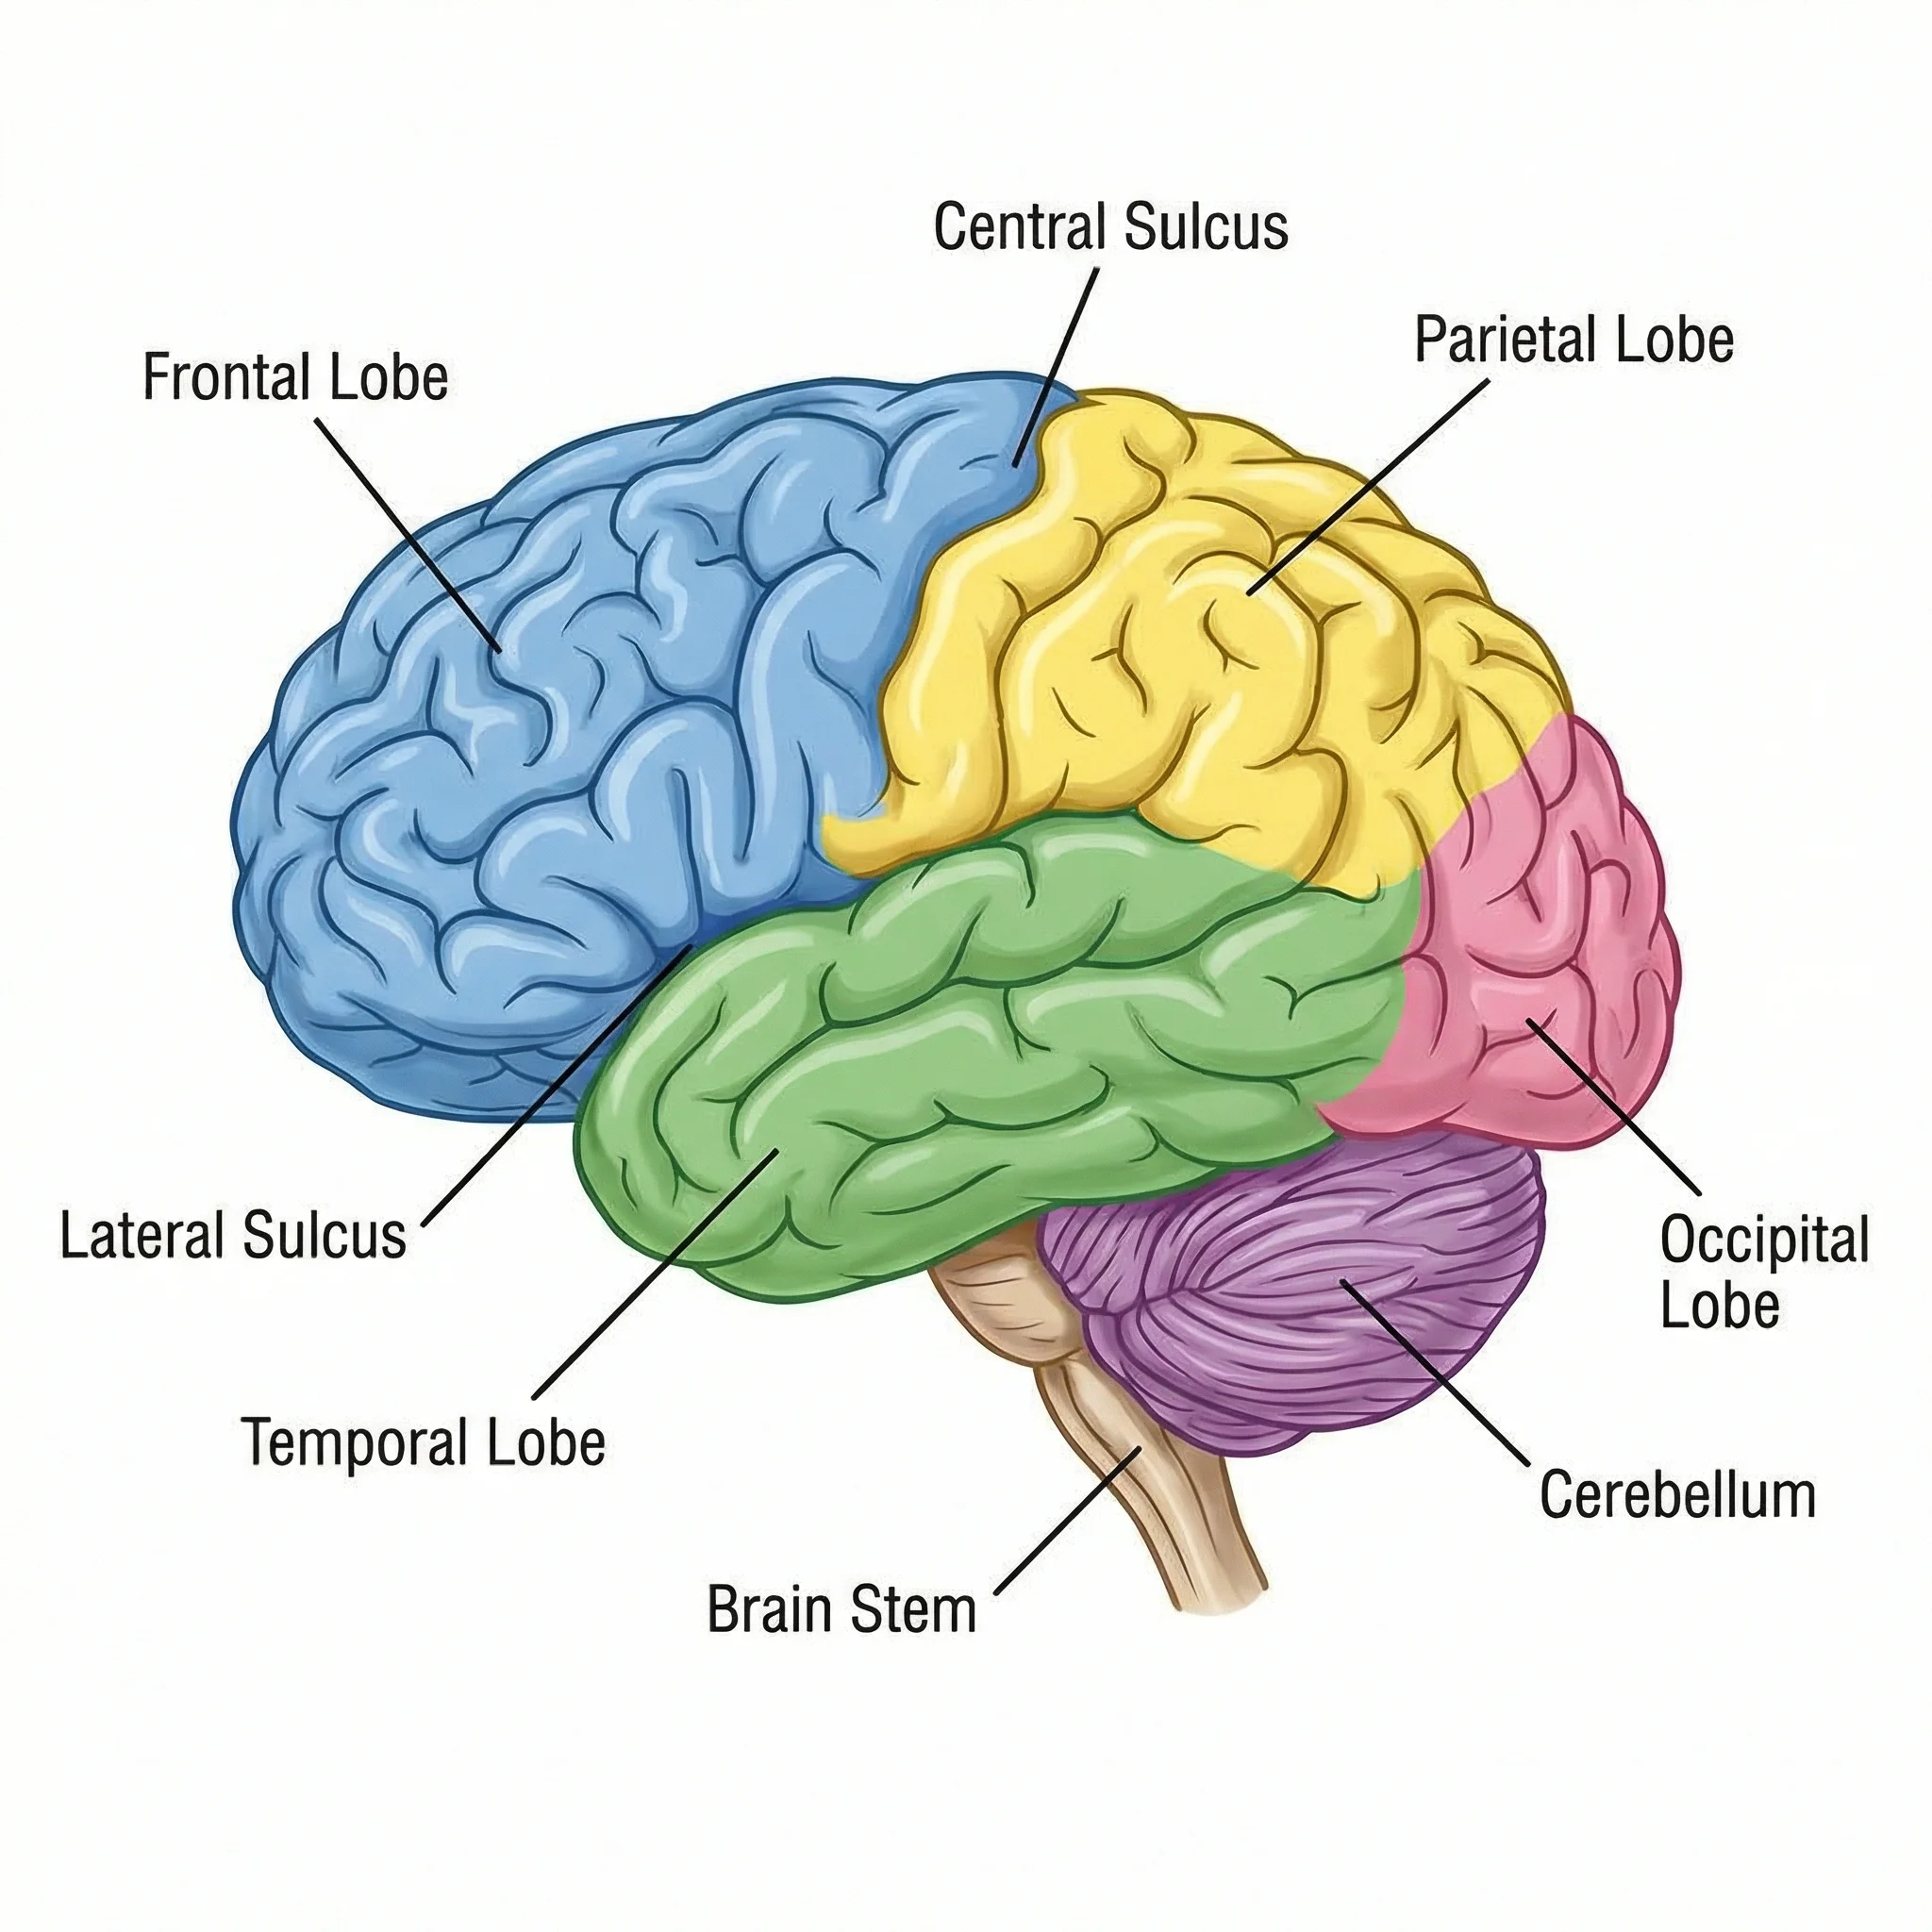

Biology

BiologyBrain Diagram Generator

Create brain anatomy and neuroscience illustrations.